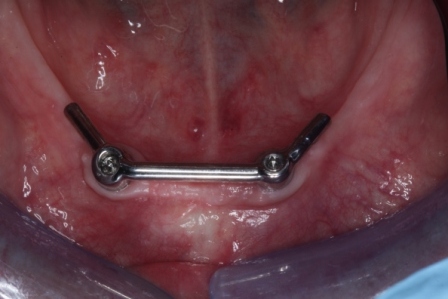

Een klikgebit (of overkappingsprothese) is een kunstgebit welke vastklikt op een aantal implantaten. In de onderkaak zit het klikgebit meestal vast op 2 of 3 implantaten, in de bovenkaak op 4 of 6 implantaten. Tussen deze implantaten wordt een staafje (ook wel steg genoemd) gemaakt waar het klikgebit dan op vast klikt. Soms wordt er in plaats van een steg gekozen voor drukknoppen. Een klikgebit zit zo vast dat het niet meer in de mond beweegt of vanzelf los kan komen. Het moet wel elke dag uit de mond genomen worden om schoon te maken en om de implantaten te borstelen.

Situatie na: klikgebit onderkaak